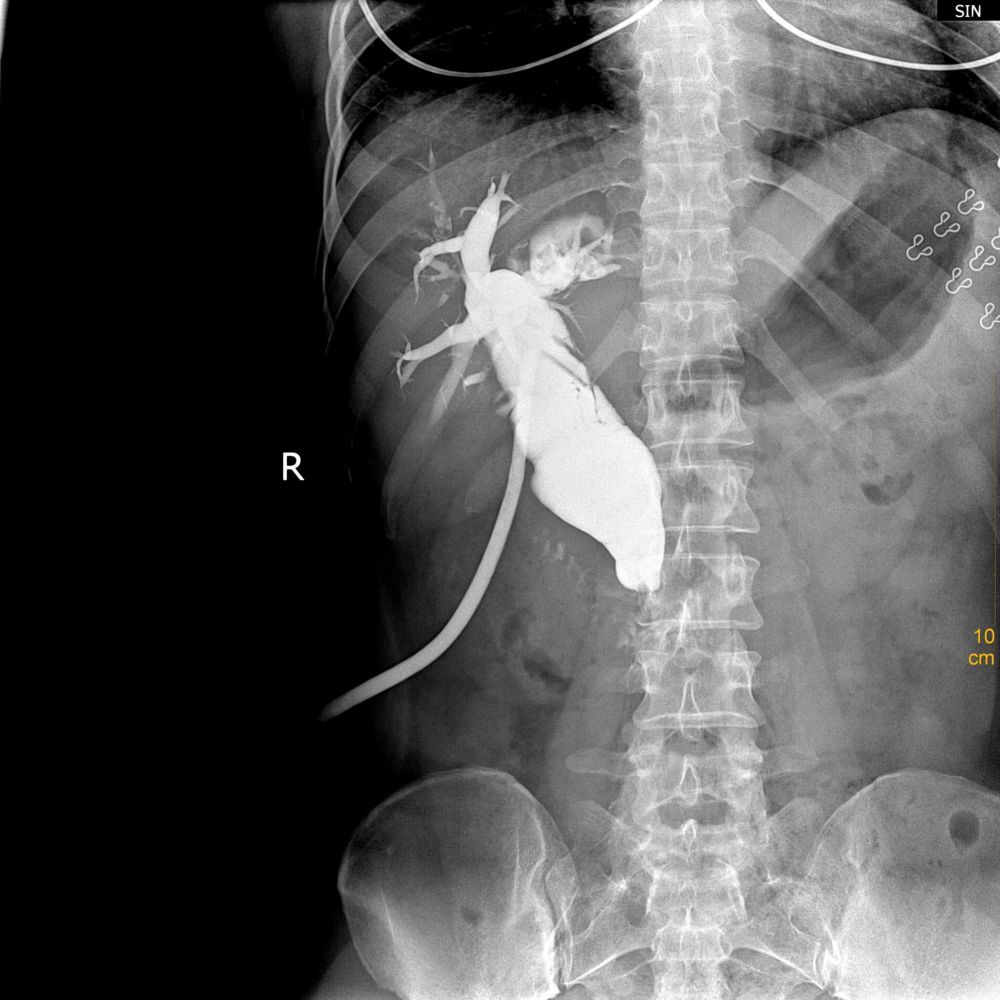

以下是引用随光逐影在2010-10-2 8:05:00的发言:[br]1)胆系术后t管留置。2)胆总管扩张。3)考虑胆总管末端炎性狭窄。

以下是引用ghp3522在2010-10-1 20:55:00的发言:[br]胆总管明显扩张,可疑胆总管末端结石狭窄。